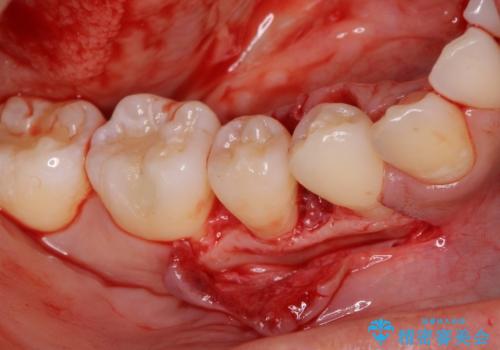

患者様は、他院で右下の歯を抜歯かもと言われました。全体の歯周病はなく、右下の1歯だけ骨が極端に減少していました(初診時歯周ポケット7mm。通常は3mm以下。)。その歯だけ咬合が強いことが原因と考えられたため、咬合を弱くする処置と減少した骨を再生する処置が必要になりました。

骨の再生治療手術をして10か月経過観察をしたのち、骨を平坦化する手術を行い、治療終了となりました。

・再生治療は、局所的な骨の減少が対象となります。

・再生治療は、10か月経過観察をする必要があります。

・手術後はしばらくワイヤー等で固定する必要があります。